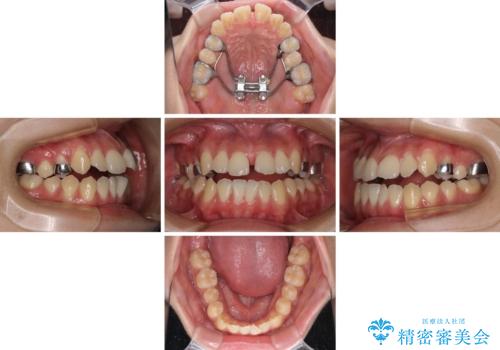

受け口と開咬を急速拡大装置とワイヤー装置で改善

- 前歯の開咬と、受け口による咬み合わせの悪さを気にして来院された患者様です。

上顎歯列が狭窄していたため、急速拡大装置により上顎骨を側方に拡大し、その後ワイヤー装置にて矯正治療を行うこととしました。